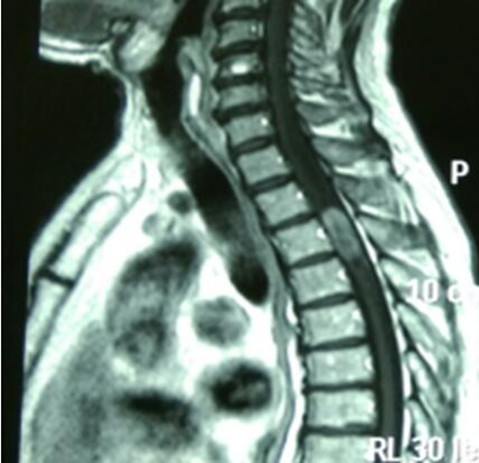

李先生53岁,入院前两个月出现肢体麻木、无力的症状,在个人诊所行针灸、按摩等治疗后症状略缓解。入院前一周,李先生肢体麻木、无力的症状加重,且行走不稳,李先生及家人这才意识到问题严重,想到北京或哈尔滨等大医院就医,但是由于经济方面的原因不能实现,于是多方打听后方知我院可以做这方面的手术,便立即来我院寻求救治。经MRI检查显示:“C2水平椎管内占位性病变”。白玉江主任团队经过反复术前讨论后决定为李先生行后路椎板切开减压、硬膜切开、肿物切除术。手术过程非常顺利。术后病理检查回报:(椎管内)脑膜瘤。每一个月随访至六个月,李先生恢复良好,无复发。

手术难度:该肿瘤已占椎管的90%,严重压迫脊髓,影响患者肢体感觉及运动,若肿瘤继续生长持续压迫脊髓,因病变节段高,可导致膈肌运动消失,以致呼吸衰竭,危及患者生命。手术风险极大,术中操作需格外谨慎,若强行切除肿瘤损伤脊髓,患者有呼吸停止的可能;此外因脊髓长期持续受压迫,一旦解除压迫,还需防止脊髓再灌注损伤的可能,若发生再灌注损伤则导致患者呼吸停止、死亡。

术前颈椎MRI